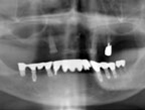

Case.03 オールオン4+即日完了治療症例

初診時

上顎は歯がすべてない状態で総義歯、下顎は大臼歯部に歯が無く小臼歯部に2本づつインプラントが埋入された状態で来院されました。上顎のインプラント治療を希望されていましたが、パノラマレントゲンでは上顎の骨の状態を診断することは不可能でした。そのためCT撮影を行いコンピュータ・シミュレーションで治療計画を立てることにしました。

レントゲン